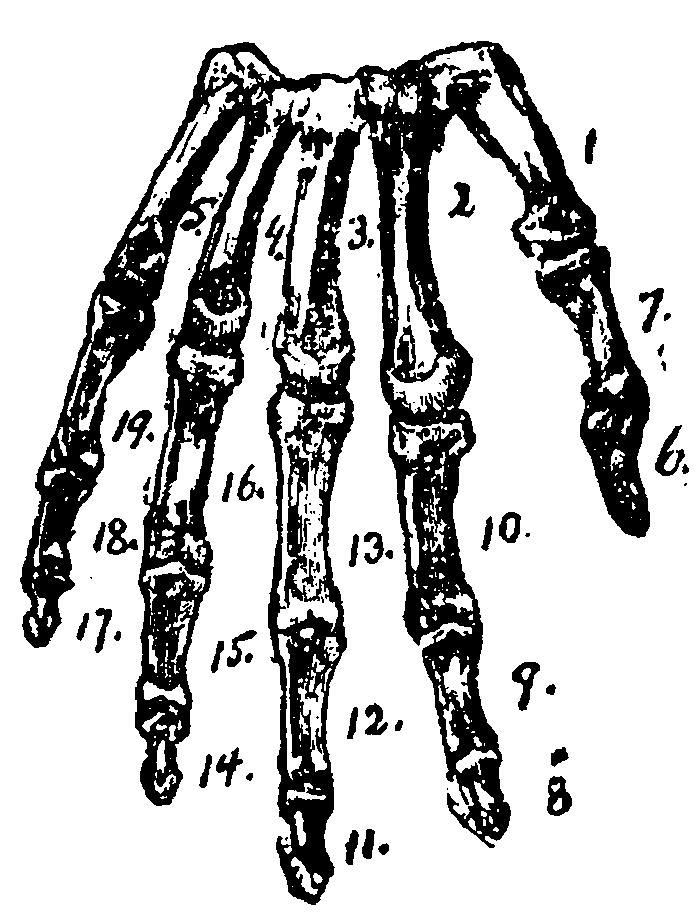

4. My upper arm has one bone; my fore-arm has two bones; my wrist has eight bones; from my wrist to my knuckles are five bones; my thumb has two bones; each finger has three bones, making nineteen bones in my hand.

FIG. B.

FIG. B.

1, 2, 3, 4, 5, the bones of the palm of the hand.

6, 7, the bones of the thumb.

8, 9, 10, the bones of the first or fore-finger.

11, 12, 13, the bones of the second or middle finger.

14, 15, 16, the bones of the third or ring finger.

17, 18, 19, the bones of the fourth or little finger.

EXERCISE FOR COUNTING THE BONES OF THE HAND.

FOR PRIMARY CLASSES.

I.

1. Close both hands.

2. Raise the forefinger of the right hand, as the index or pointing finger.

3. Place the index finger upon the lower thumb joint of the left hand.

4. Draw the index finger down to the wrist, over the bone between the thumb knuckle and the wrist, and count "One."

5. Place the index finger on the knuckle of the first finger.

6. Draw the index finger down to the wrist, over the bone leading from the first finger to the wrist, and count "Two."

7. So on, for each of the three other bones of the hand. Repeat until no mistake is made in touching or counting.

II.

1. Raise the thumb, and place the index finger of the right hand on the middle of the upper part of the thumb for bone "Six"; then

2. On the lower part of the thumb for bone "Seven." Repeat from the beginning, until the children can touch and count each bone properly.

III.

1. Keep the thumb erect; raise the first finger of the left hand.

2. Place the index finger on the bone between the tip and the first joint of the first finger for bone "Eight."

3. Between the first and middle joint for bone "Nine."

4. Between the middle and third joint for bone "Ten." Review, from the beginning, until the class can touch and count every bone as directed.

IV.

1. Keep the thumb and forefinger erect; raise the second finger and touch, as in the lesson on the first finger bones, "Eleven," "Twelve," and "Thirteen." Review. [19]

2. Proceed in the same manner for the third and fourth fingers, always beginning with the bone nearest the tip of the finger, and touching that at the lowest part last.

If the exercise has been properly performed, every child will say "Nineteen" as its index finger touches the lowest bone of the little finger, and all the fingers of every left hand will be outspread.